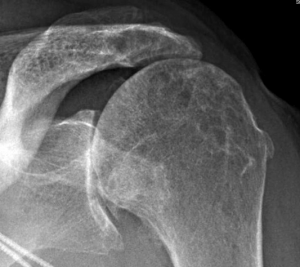

Bijkomend ontstaat er een indeuking in de bol (humeruskop) van de schouder omdat deze tijdens de ontwrichting tegen de rand van de kom (glenoid) wordt geduwd (hill sachs letsel). Bij oudere mensen kan een ontwrichting ook gepaard gaan met een scheur in de rotator cuff.

Indien er reeds meerdere ontwrichtingen zijn geweest is de kans groter dat er reeds schade is ontstaan in het schouder gewricht (bv. bankart letsel). Hoe jonger je was bij de eerste ontwrichting, hoe groter de kans dat er nog bijkomende ontwrichtingen volgen. Hoe meer ontwrichtingen er zijn geweest, hoe groter de kans op schade in het gewricht en hoe groter de kans op artrose op latere leeftijd. Ook je sportactiviteiten of beroepsactiviteiten kunnen je vatbaar maken voor nieuwe ontwrichtingen en kunnen beslissend zijn voor de verdere behandeling (bv. bij een rugby speler is de kans op nieuwe ontwrichting groter dan bij een loper).